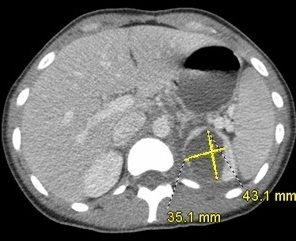

A 3.5 x 4-cm cyst in the upper pole of the left kidney was detected by renal ultrasonography. This raised concern for a possible renal abscess, given the patient’s clinical picture. A CT scan of the abdomen/pelvis with contrast revealed a left renal abscess (43.1 x 35.1 cm2) (Figure).